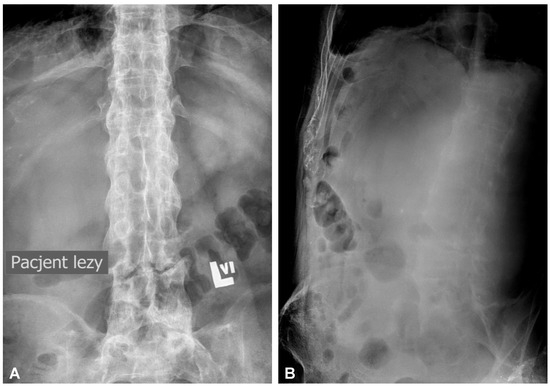

A 59-year-old man presented to the hospital with atypical abdominal pain for a few days, three weeks after sustaining a low-energy fall. At the time of admission, the patient had normal upper and lower extremity strength and no pathologic reflexes, as well as no bowel or bladder incontinence. The initial performed plain radiograph of the abdomen demonstrated a fracture line completely slicing through the L3/L4 intervertebral disc space and features of ASH (Figure 1). The additional performed computed tomography (CT) scans demonstrated a three-column fracture of L4 vertebrae with a suspicious transdiscal injury at the L3/L4 level, which was morphologically classified as type B3/C according to the Arbeitsgemeinschaft für Osteosynthesefragen (AO) spine classification. Moreover, at the fracture level, the hypodense area communicating intervertebral disc space with both psoas major muscles forming a massive, well-defined fluid-like collection in the right retroperitoneum was observed (Figure 2). In addition, contrast-enhanced CT (CE-CT) showed a thick enhancing wall and internal septae within an area measuring a total of 10 cm × 20 cm × 10 cm (TR × AP × CC) (Figure 3). Furthermore, the performed magnetic resonance imaging (MRI) scans confirmed the cystic nature of the lesion, which had no specific characteristics and demonstrated intensities that were similar to those of cerebrospinal fluid (CSF) (Figure 4). Taking into consideration the history and radiological features, suspicion of spondylodiscitis with osteomyelitis features and retroperitoneal abscess formation was provided by the radiologist. Blood analysis performed on admission revealed the following results: hemoglobin (Hb): 9.6 g/dL; platelet (PLT): 192 × 109/L; white blood cell (WBC): 9.7 × 109/L; and creatinine (CREA): 0.42 mg/dL. Despite the lack of infection symptoms, the patient was empirically administered intravenous antibiotics, including meropenem (1 g every 8 h) and vanomycin (1 g every 12 h), without waiting for microbiological confirmation.

Figure 1. Initial anteroposterior (A) and lateral (B) plain radiographs of the lumbar spine demonstrating fracture line completely slicing through the L3/L4 intervertebral disc space and features of the extensive calcification and ossification along the vertebral column resembling classic “bamboo spine” formation.